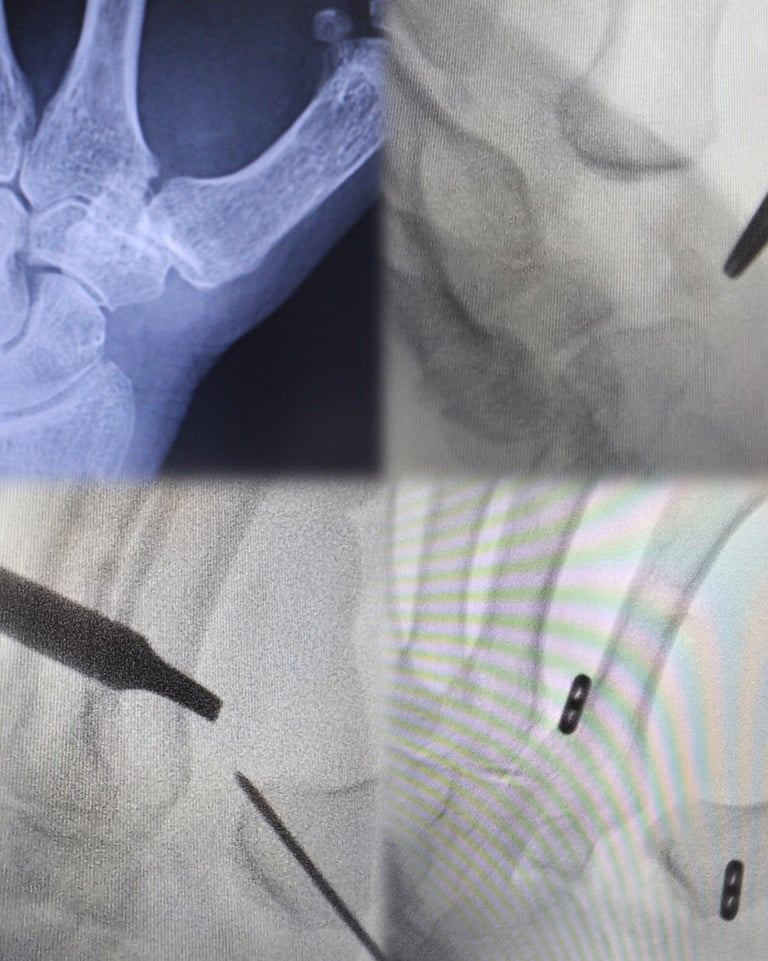

Una técnica mínimamente invasiva para la rizartrosis

A través de pequeñas incisiones y bajo visualización artroscópica, se reseca únicamente la porción patológica del trapecio, conservando la estabilidad y la biomecánica del pulgar. Esta técnica permite un menor dolor postoperatorio, movilización precoz y una recuperación funcional más rápida en comparación con técnicas abiertas más agresivas.

¿Quién es el paciente ideal para esta intervención?

Pacientes jóvenes o activos, entre 45-55 años que desean preservar la articulación y evitar cirugías más radicales.

Rizartrosis en estadios iniciales o moderados (Eaton I–II, algunos III seleccionados).

Dolor persistente que limita actividades finas o de fuerza a pesar de tratamientos conservadores.

Buena estabilidad metacarpiana sin colapso avanzado ni deformidad fija.

Pacientes que requieren recuperación rápida por motivos laborales o deportivos.